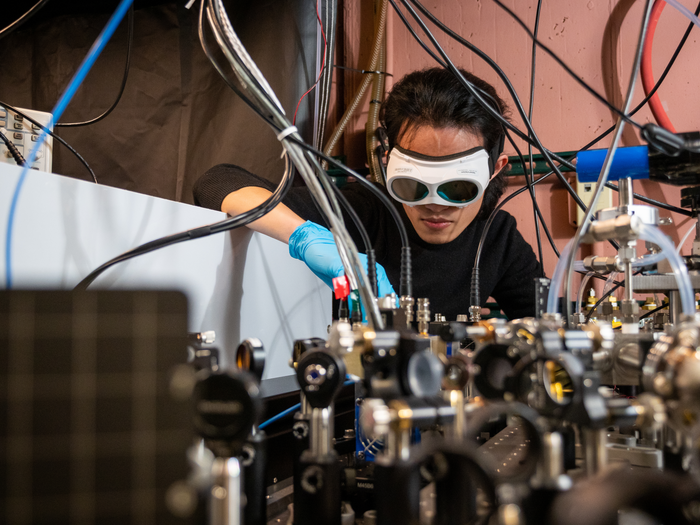

Currently, however, the “breathalyser” consists of a complex array of lasers and mirrors – and is the size of a banquet table.

A breath sample is piped in through a tube as lasers fire invisible mid-infrared light at it at thousands of different frequencies. Dozens of tiny mirrors bounce the light back and forth through the molecules so many times that in the end, the light travels about 1.5 miles.

Because each kind of molecule absorbs light differently, breath samples with different molecular makeup make their own distinct shadows.

The machine can distinguish between those different shadows or absorption patterns, boiling millions of data points down to a simple positive or negative result, in a matter of seconds.